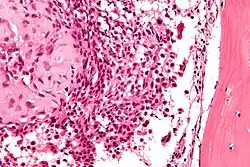

Micrograph of a chondroblastoma. H&E stain.

Chondroid differentiation is a common feature of chondroblastoma.[1][4][6] A typical histological appearance consists of a combination of oval mononuclear and multi-nucleated osteoclast-type giant cells.[1][3][4] However this is not a prerequisite for diagnosis, as cells with epithelioid characteristics have been observed in lesions of the skull and facial bones.[4] A "chicken-wire" appearance is characteristic of chondroblastoma cells and is the result of dystrophic calcification that may surround individual cells.[1][5] Although, calcification may not be present and is not a prerequisite for diagnosis.[1][3][4] Mitotic figures can be observed in chondroblastoma tissue but are not considered atypical in nature, and therefore, should not be viewed as a sign of a more serious pathology.[1][4] There is no correlation between mitotic activity and location of the lesion.[4] Furthermore, the presence of atypical cells is rare and is not associated with malignant chondroblastoma.[1][6]